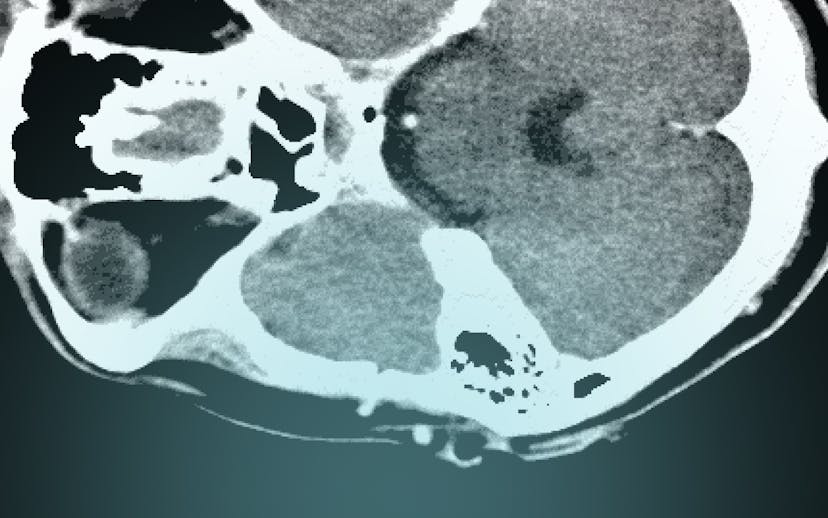

Marc Trabsky and Averyl Gaylor have co-authored a journal article for Social & Legal Studies that examines how radiological images became accepted by courts as visual evidence of death in the 20th century. Initially conceived as a speciality of photography, X-rays confounded courts, eliciting a range of judicial responses, from outright refusal to consider the images as any kind of evidence, to mocking them as cheap parlour tricks for an unwitting public, to recognising them as more reliable than the testimony of the expert witness. The article contends that courts moved towards recognising X-rays as proof of death only by both affirming forensic radiology's promise of ‘mechanical objectivity’ while acknowledging its reliance on the fallibility of ‘human subjectivity’. It suggests that this history has broader implications in socio-legal studies for comprehending how the invention of novel optical techniques continues to problematise legal epistemologies of death in the 21st century.

Post-mortem computed tomography (PMCT) has changed the experiences of bereaved people in coronial investigations. PMCT was developed by the Virtopsy® team initially at the University of Bern, but later at the University of Zurich, in the 1990s. It has been implemented in parts of Australia, Canada, Europe, Japan, UK, and USA since the early 2000s. When the technology is used as a triage tool to decide whether a medical cause of death can be found through CT scanning and an external examination of the body, it can decrease the rate of invasive autopsies in the coronial jurisdiction. For example, when the Victorian Institute of Forensic Medicine, located in Melbourne, Australia, introduced PMCT in 2005, the autopsy rate decreased by approximately 50%, and the rate of objections to autopsies by the next of kin also diminished.

Speaking before forensic scientists, Marc discussed the scope of his project on Virtual Autopsies and explained that post-mortem computed tomography has an important role in enabling coroners to meet the statutory objectives of coronial law, make recommendations for reducing the occurrence of preventable deaths, and carry out the administration of coronial justice.

Marc argued that virtual autopsies are inherently auto-optos, or to put this differently, they create the allure that judicial observers can see the interiority of the corpse with their own eyes. On the one hand, the post-mortem computed tomography appears to be more ‘objective’ than analogue technologies in determining the cause of a death. Yet on the other hand, like the images themselves which compose a body from multiple slices of data, ‘objectivity’ only takes shape through the mediation of mechanical instruments, computational techniques, and the medico-legal expert.